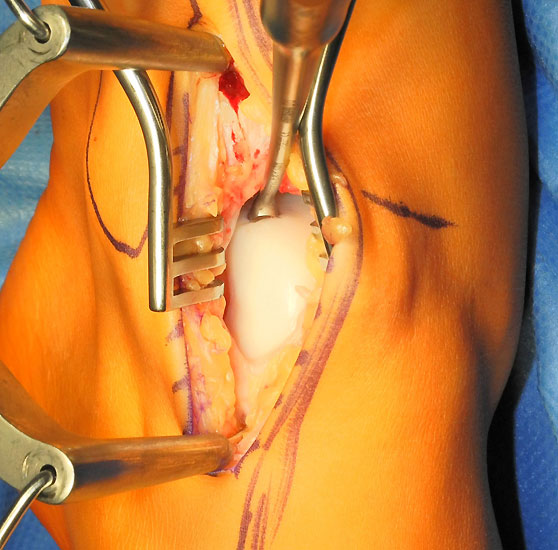

Je nach Lage des Knorpeldefektes sind verschiedene Zugänge möglich. Ziel ist einen guten Zugang zum Defekt zu erreichen bei gleichzeitiger Vermeidung einer Innenknöchelosteotomie.

Die Darstellung der weiteren Operationstechnik erfolgt am Beispiel eines medialen Zugangs bei einer Osteochondrosis dissceans mit subchondraler Zyte der medialen Talusschulter (siehe MRT Abbildung 1).